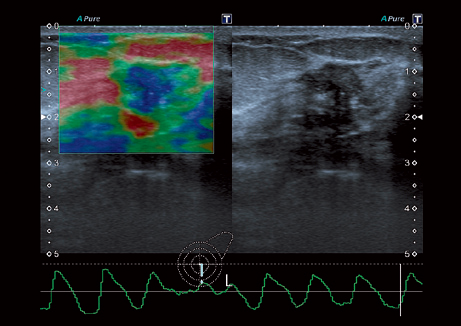

• ApliPure - технология повышения качества изображения

• Эластография